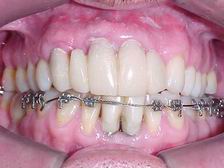

Aspecto final após glazeamento da cerâmica e remoção do aparelho ortodôntico

Metalocerâmica sobre implantes (CONCLUÍDO)